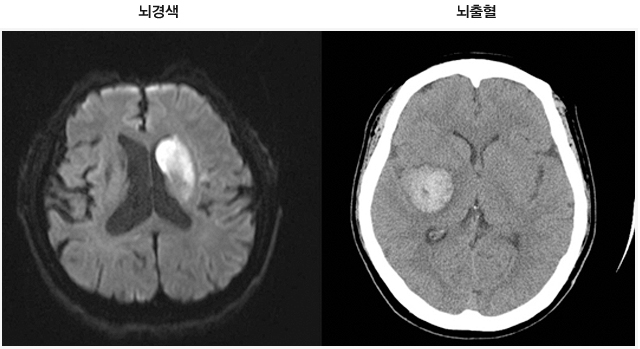

먼저 뇌경색이 무엇인지에 대해 쉽게 설명드리겠습니다. 뇌경색은 뇌로 가는 혈류가 차단되어 발생하는 질병으로, 일반적으로 뇌졸중이라고도 알려져 있습니다. 뇌혈관이 좁아지거나 막히면서 뇌가 필요한 산소와 영양분을 공급받지 못하게 되고, 이로 인해 뇌세포가 손상됩니다. 이러한 손상은 즉각적인 신체 기능 저하를 초래할 수 있으며, 심각한 경우 생명에 지장을 줄 수 있습니다.